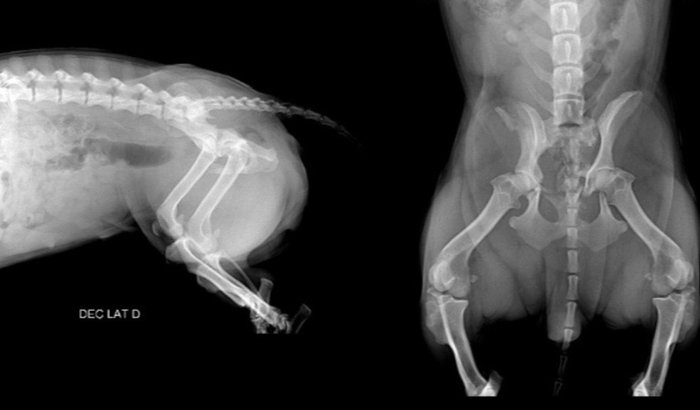

A Pandora foi atropelada e, desde então, não está conseguindo andar. Após avaliação veterinária, foi indicada cirurgia ventrodorsal e laterolateral (direita e esquerda), essencial para que ela tenha chances de voltar a se locomover e viver sem dor. O valor da cirurgia é de R$ 4.500,00, além das despesas com clínica, internação e medicações.Para mais informações entre em contato com a gente! (21) 997742853 - Patrícia (21) 975403688 - Carolina